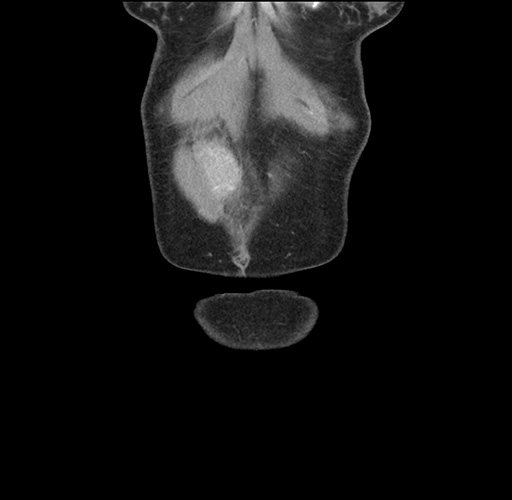

Imaging Analysis

Look through the patient's CT scan to identify any areas of concern for the necessary procedure.

Based on your CT findings, which issue(s) would give reason for "planned slowing down moment(s)" in this case?